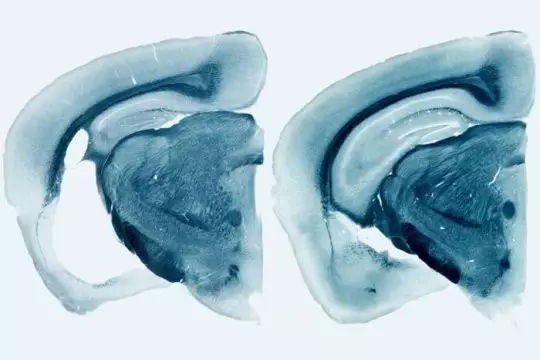

ApoE4 markedly exacerbates tau-mediated neurodegeneration in a mouse model of tauopathy

ApoE4 显著加剧 tau 蛋白病小鼠模型中 tau 介导的神经退化

图片来源:sciencedaily.com

(导读 陈月欣)APOE4 基因及其蛋白与阿茨海默症的发生有着高度的关联性,但 APOE 基因家族对包括阿茨海默症在内的 tau 蛋白疾病的具体影响还不明确。通过研究 P310S tau 转基因小鼠发现,转入 APOE 家族基因可以显著影响 tau 蛋白在脑中的分布,并提高胶质细胞的炎症水平。其中 APOE4 的影响最为明显。而敲除 APOE 基因则可以起到保护作用。